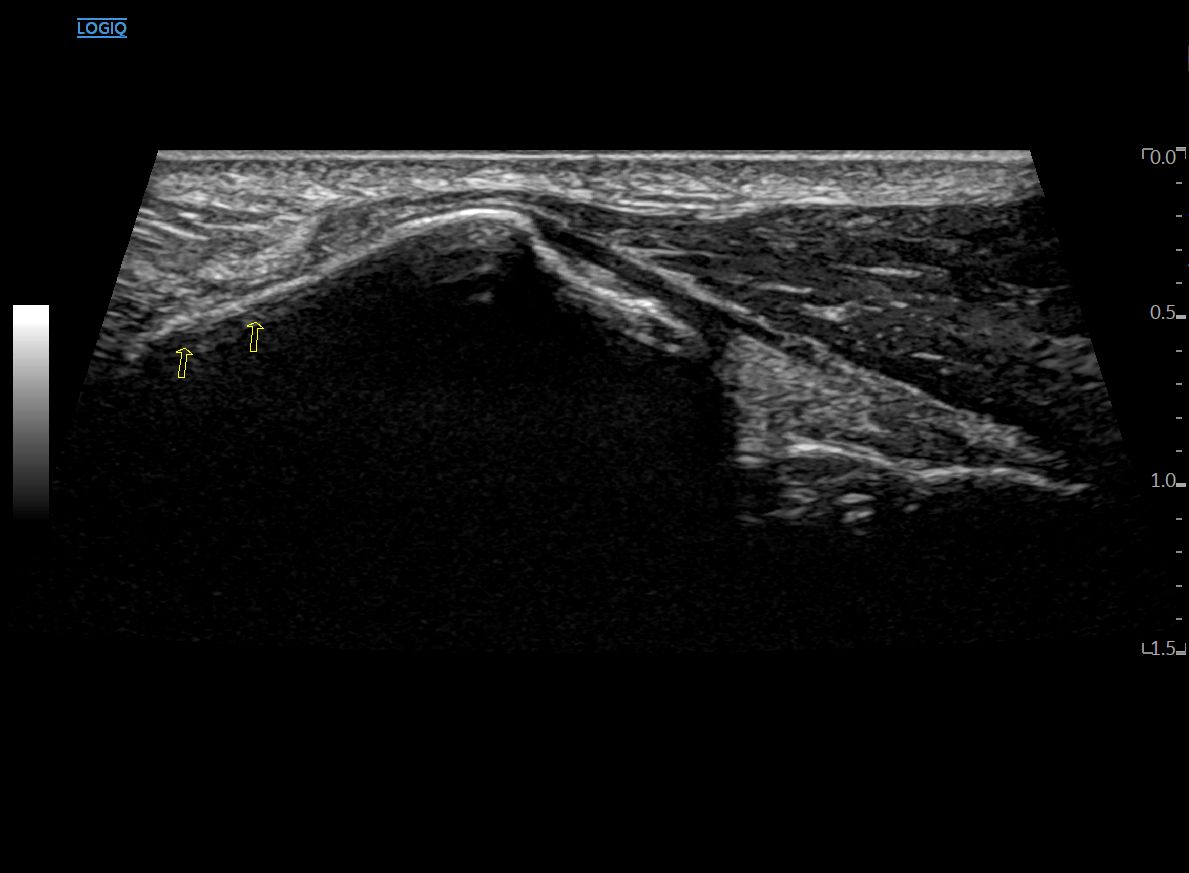

안쪽으로 프로브를 이동하면

단지신근 근복부가 크게 보이고요.

종골 Body가 새 머리 모양처럼 불쑥 솟아 오릅니다.

좀 더 올라오면

드디어 이분인대 섬유가 모습을 드러냅니다.

종골과 입방골을 연결하는

종입방인대입니다.

이 때 종골 피질이 쭉 연결되어 보이는데요.